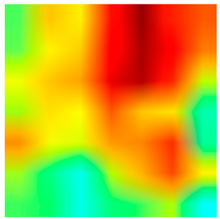

2.4. Model Interpretability

3.6. Visualizing Interpretability in CRC Classification Using ADFMs

| Tissue Class | Original Image | Heatmaps | Superimposed Image |

|  |  |  |

|  |  |  |

|  |  |  |

|  |  |  |